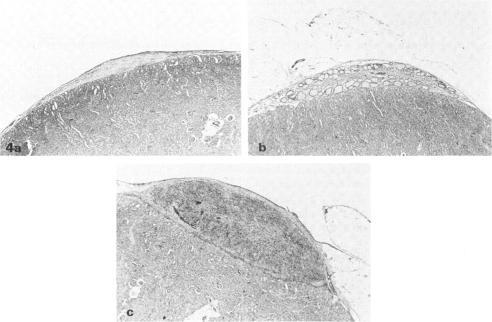

Post-irradiation transplantation of normal thyroids under the renal capsule of syngenetic thymectomized and irradiated (Tx-X) rats leads to the development of thyroiditis in the ectopic grafted thyroids. A close correlation was observed between the extent of the lesions in the grafted and recipient's own thyroid. The histopathology of both grafted and recipient thyroid was similar and was characterized by infiltration with mononuclear cells together with some plasma cells. Conversely, grafting of affected thyroids from Tx-X rats to normal animals resulted in the regression of the lesion in the graft and no evidence thyroiditis was observed in either the graft or the recipient's thyroid when these were examined 60 days post-grafting. Thyroids derived from normal animals grafted to syngenetic normal rats were found to remain healthy and intact over a 60-day period. In contrast to normal animals, Tx-X rats were unable to reject totally in transplanted allogeneic thyroids by 28 days post-grafting, suggesting that some impairment of cell-mediated immunity follows this treatment. These findings indicate that the pathological change occurring in the thyroid gland of Tx-X rats is not attributable to the local effect of irradiation of the thyroids and adds further support to the concept that the process is immunologically mediated by thyroid-specific circulating components in the absence of normal immune regulatory function.

在同基因胸腺切除并受照射(Tx-X)的大鼠肾被膜下移植正常甲状腺,会导致异位移植的甲状腺发生甲状腺炎。观察到移植甲状腺和受体自身甲状腺的病变程度之间存在密切相关性。移植甲状腺和受体甲状腺的组织病理学相似,其特征为单核细胞连同一些浆细胞浸润。相反,将Tx-X大鼠的病变甲状腺移植到正常动物体内,会导致移植甲状腺的病变消退,并且在移植后60天检查时,无论是移植甲状腺还是受体甲状腺,均未观察到甲状腺炎的迹象。将正常动物的甲状腺移植到同基因正常大鼠体内,发现这些甲状腺在60天内保持健康完整。与正常动物不同,Tx-X大鼠在移植后28天内无法完全排斥移植的同种异体甲状腺,这表明这种处理会导致细胞介导免疫的某种损伤。这些发现表明,Tx-X大鼠甲状腺发生的病理变化并非归因于甲状腺局部照射的影响,进一步支持了这样一种概念,即该过程是在缺乏正常免疫调节功能的情况下,由甲状腺特异性循环成分免疫介导的。